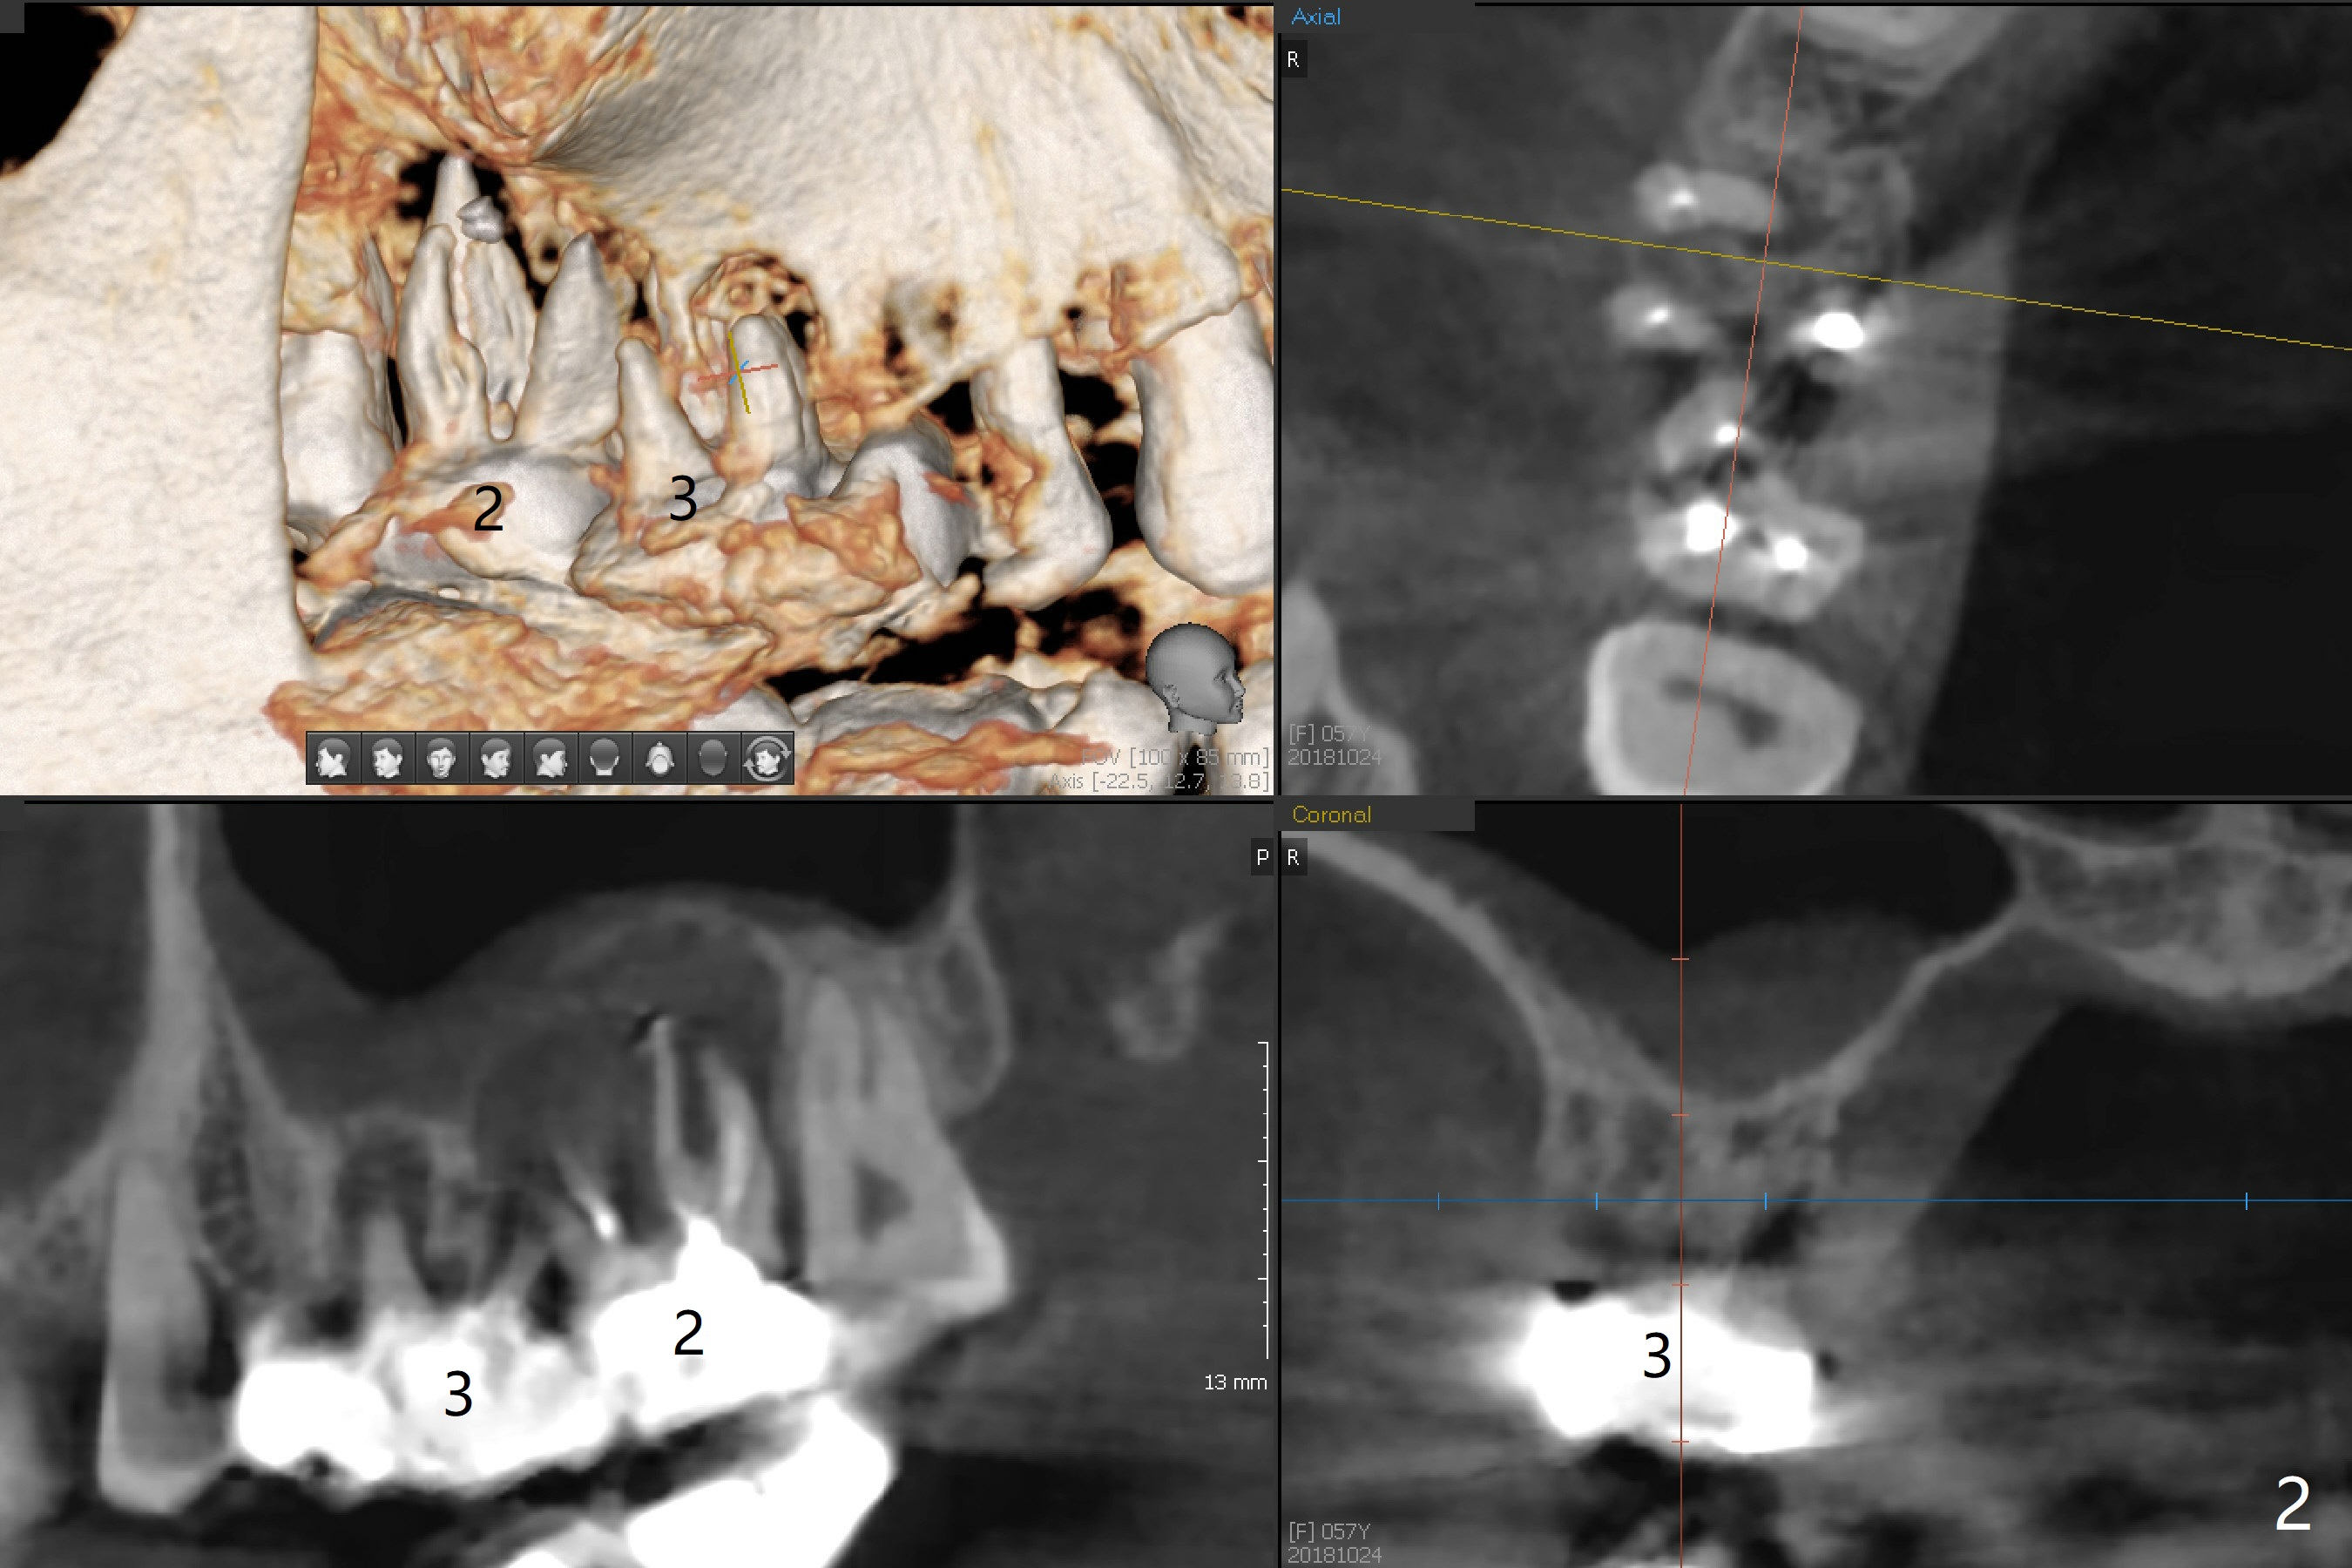

A 57-year-old woman returns with pain in the upper right quadrant (Fig.1,2). In fact the mesiobuccal root of the tooth #2 has vertical fracture. Although the socket destruction at #3 is not as extensive as that of #2, the socket of #3 has communication with the sinus. Prior to socket preservation, a piece of Osteogen plug is inserted at #3. PRF should be prepared for severe bone loss. In contrast there is no bone loss around the implants at #19 or #30 (Fig.1,3,4). Although the socket at #2 is slightly open 9 days postop, bone graft appears to be present (Fig.5). The bone at #2 and 3 seems to regenerate 7 months post socket preservation (Fig.6). Three short implants seem to be better than 2 implants for 3-unit FPD (Fig.7-9).